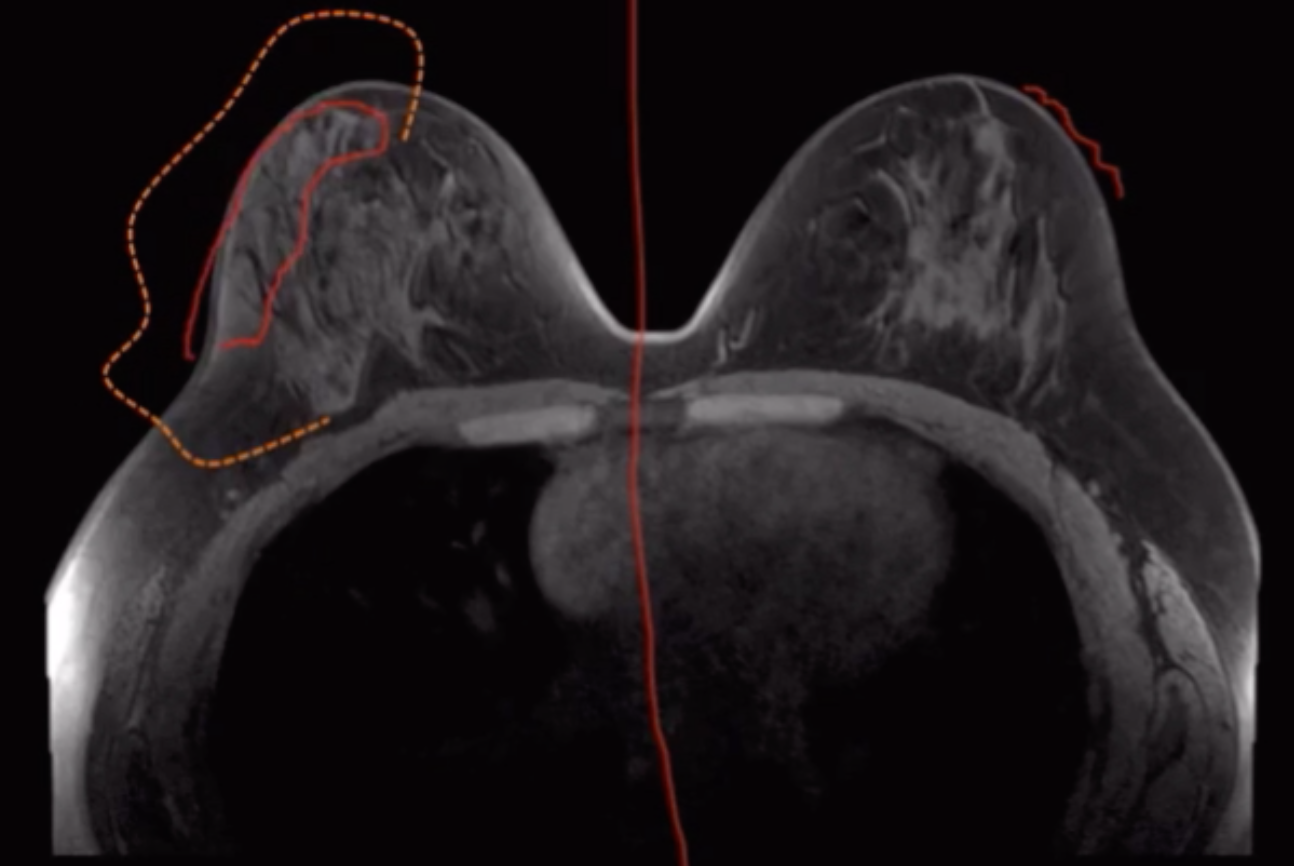

Rebound/Flare Affect

• When on tamoxifen breast tissue is suppressed

• When off tamoxifen breast tissue will go back to normal and get bigger